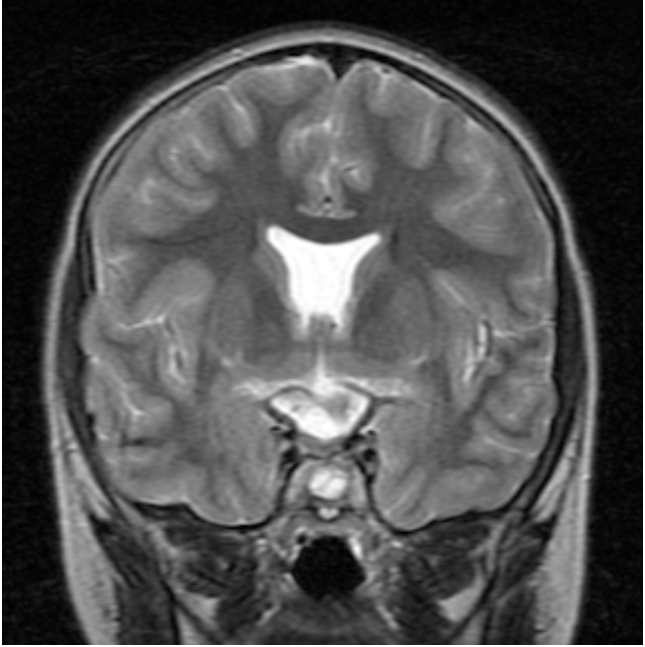

Figure 2: Coronal T2W image of the brain demonstrating absence of the septum pellucidum in septo-optic dysplasia.